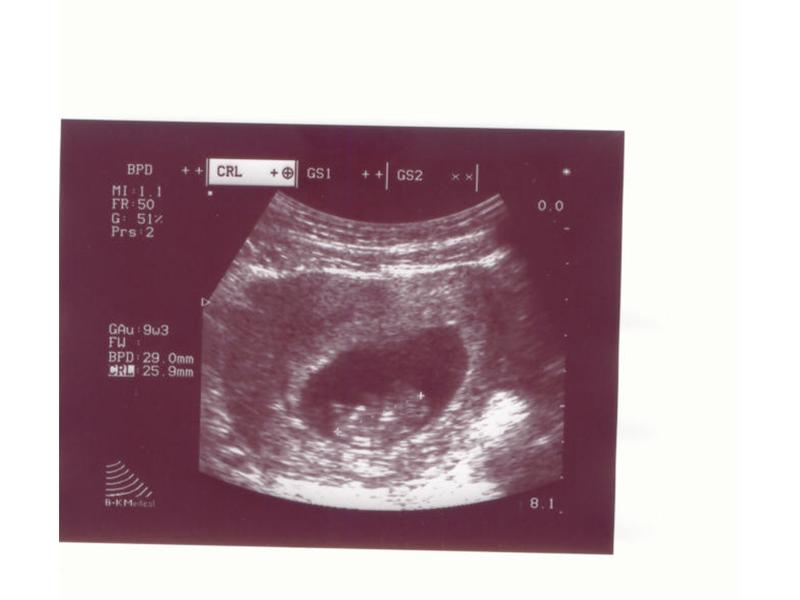

Zdroj: archiv redakce